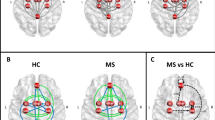

8 components resembling well-described resting state networks were chosen for further analysis, namely: the default mode, dorsal attention, sensorimotor, auditory, medial and lateral visual, executive-control/salience and frontoparietal networks (see Fig. 1 for the spatial maps of these networks). The sensorimotor network showed significantly decreased connectivity in the parietal operculum and near the primary auditory cortex in the MS group (p < 0.013; see Fig. 2).

Group independent component analysis and dual regression results. A The group ICA analysis produced 8 components resembling previously described resting state networks (from left-to-right): the default mode, dorsal attention, lateral/medial visual, auditory, sensorimotor, frontoparietal and executive networks. Network maps were overlaid on the MNI152 standard template. The color bar depicts Z-values. The sensorimotor network (highlighted in gray) showed reduced connectivity in the MS group (max. voxel MNI coordinates: x = -38 y = -30 z = 4). B Altered connectivity of the SMN in the MS group. The SMN spatial map (transparent) and clusters showing significant connectivity differences were overlaid on the MNI152 standard template. The color bar depicts T-statistics

Functional Laterality—Group Differences

Functional laterality in the default mode network was significantly decreased in the MS group in the angular gyrus and inferior parietal lobule, indicating a leftward shift in connectivity (p < 0.005, corrected for multiple comparisons). Laterality of the dorsal attention network was significantly diminished in the MS group in the posterior intraparietal sulcus, also indicating a leftward shift of functional laterality (p < 0.033, corrected for multiple comparisons). We subsequently tested whether mean laterality indices underlying the group difference cluster show express lateralisation to the right or left in either group using a two-tailed Wilcoxon signed rank test. The group difference cluster in the default mode network was not significantly lateralized in the healthy group, whereas it showed significant leftward dominance in the MS group (p < 0.001). Laterality of the group difference cluster in the dorsal attention network was significantly right side dominant in the healthy group (p < 0.001) and it did not express significant lateralisation in the MS group. Figure 2 shows the locations of altered laterality (Fig. 3).

Altered functional laterality in the MS group. Clusters showing significant group differences in functional laterality were superimposed on the symmetric ICBM 2009 template and the symmetrised network masks (depicted in red); blue-light blue clusters show MS < HC (max. voxel MNI coordinates: default mode network – x = 48 y = − 74 z = 28; dorsal attention network – x = 34 y = − 84 z = 32). Color bars depict T-statistics. Boxplots depict mean laterality indices in the two groups that underlie clusters of significant group differences